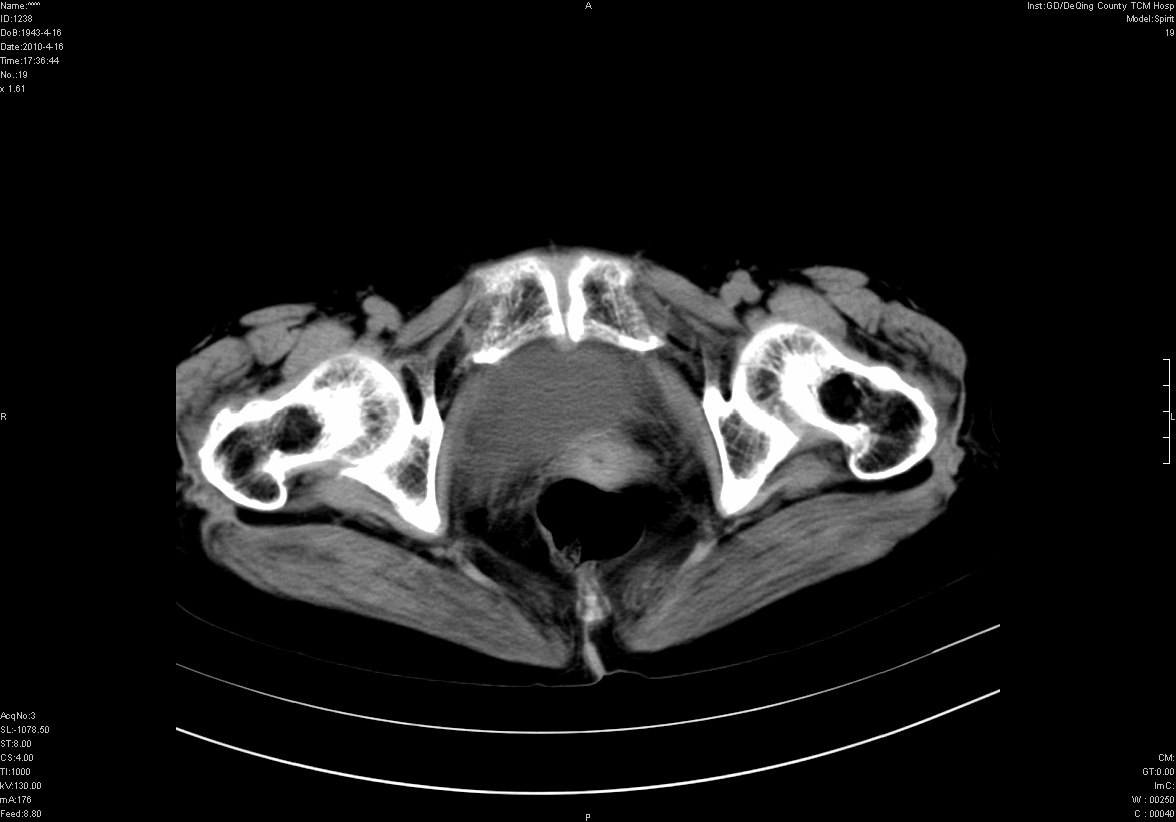

标题: CT25796:女,60岁,腹痛5天,请会诊??? [打印本页]

标题: CT25796:女,60岁,腹痛5天,请会诊???

考虑卵巢畸胎瘤。

支持右侧盆腔畸胎瘤。

畸胎瘤

右侧附件畸胎瘤

考虑右侧卵巢畸胎瘤。

考虑右侧卵巢畸胎瘤

右侧卵巢畸胎瘤可能。